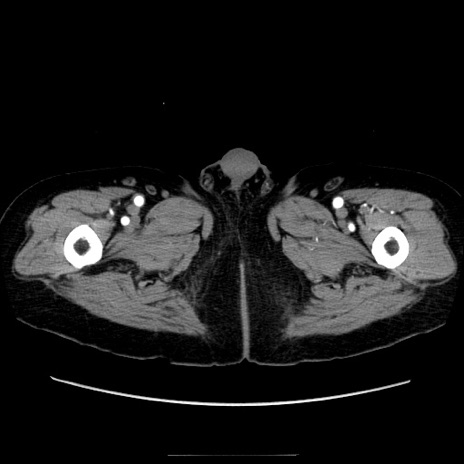

症例21(横断像)

【症例】70歳代男性

【主訴】腹痛

【現病歴】肝硬変・肝細胞癌にてかかりつけの方。約9時間前に食後より腹痛出現。症状が徐々に増悪し、嘔吐出現したため来院。

【既往歴】肝硬変、肝細胞癌(RFA、TACE後)

【身体所見】意識清明、表情苦悶様、BT 36℃、BP 129/78mmHg、P 88bpm、SpO2 97%(RA)、右上腹部から心窩部にかけて圧痛あり、反跳痛なし、筋性防御あり。

【データ】WBC 5800、CRP 0.16